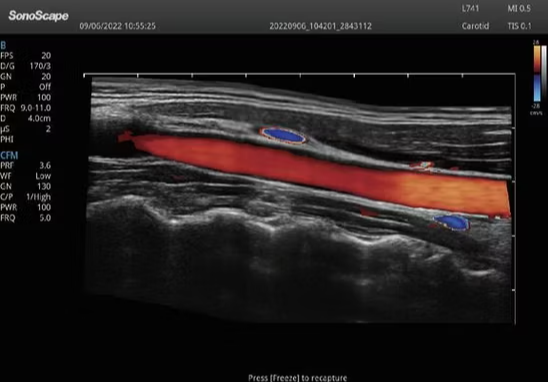

- Applications: Cardiology, OB/GYN, abdominal, vascular, veterinary imaging

The P12 Elite uses advanced ultrasound imaging technology to deliver clear, detailed, and accurate diagnostic images. This helps doctors detect diseases faster and improve clinical outcomes.

2. High-Resolution Display

The machine features a large high-definition LED monitor that allows medical professionals to analyze images with exceptional clarity.

Cardiology

Provides detailed heart imaging and strain assessment to support accurate cardiovascular diagnosis.

Applications: Cardiology, OB/GYN, abdominal, vascular, veterinary imaging

Imaging Modes: Advanced ultrasound imaging technology